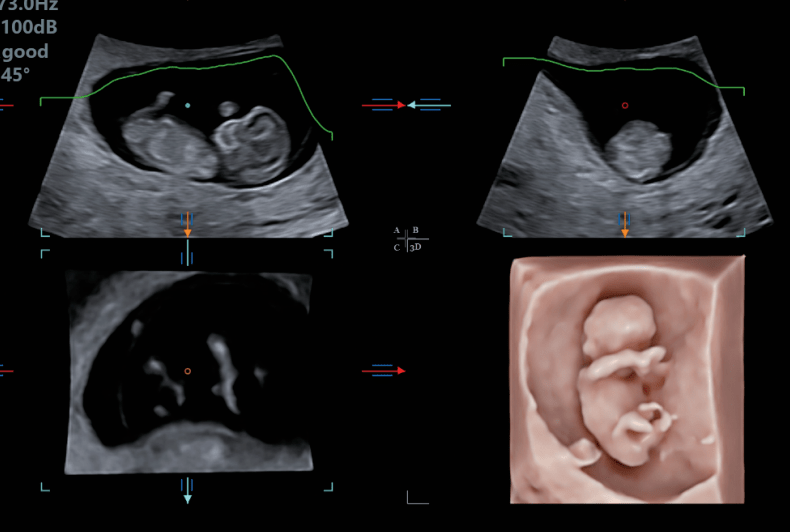

胎儿三维超声

运用3d4d成像技术,实现全方位多角度观察胎儿;自动测量胎儿颈项透明层